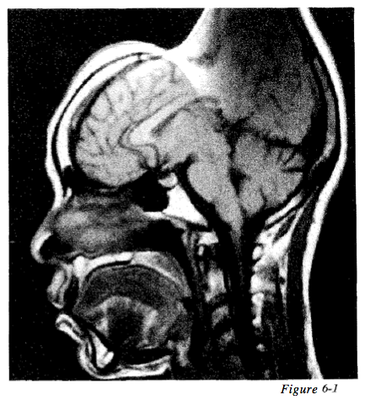

Question 56

Question

Figure 6 - 1 displays an example of what type of artifact?

Answer

• Aliasing

• Truncation

• Foldover

• Magnetic Susceptibility